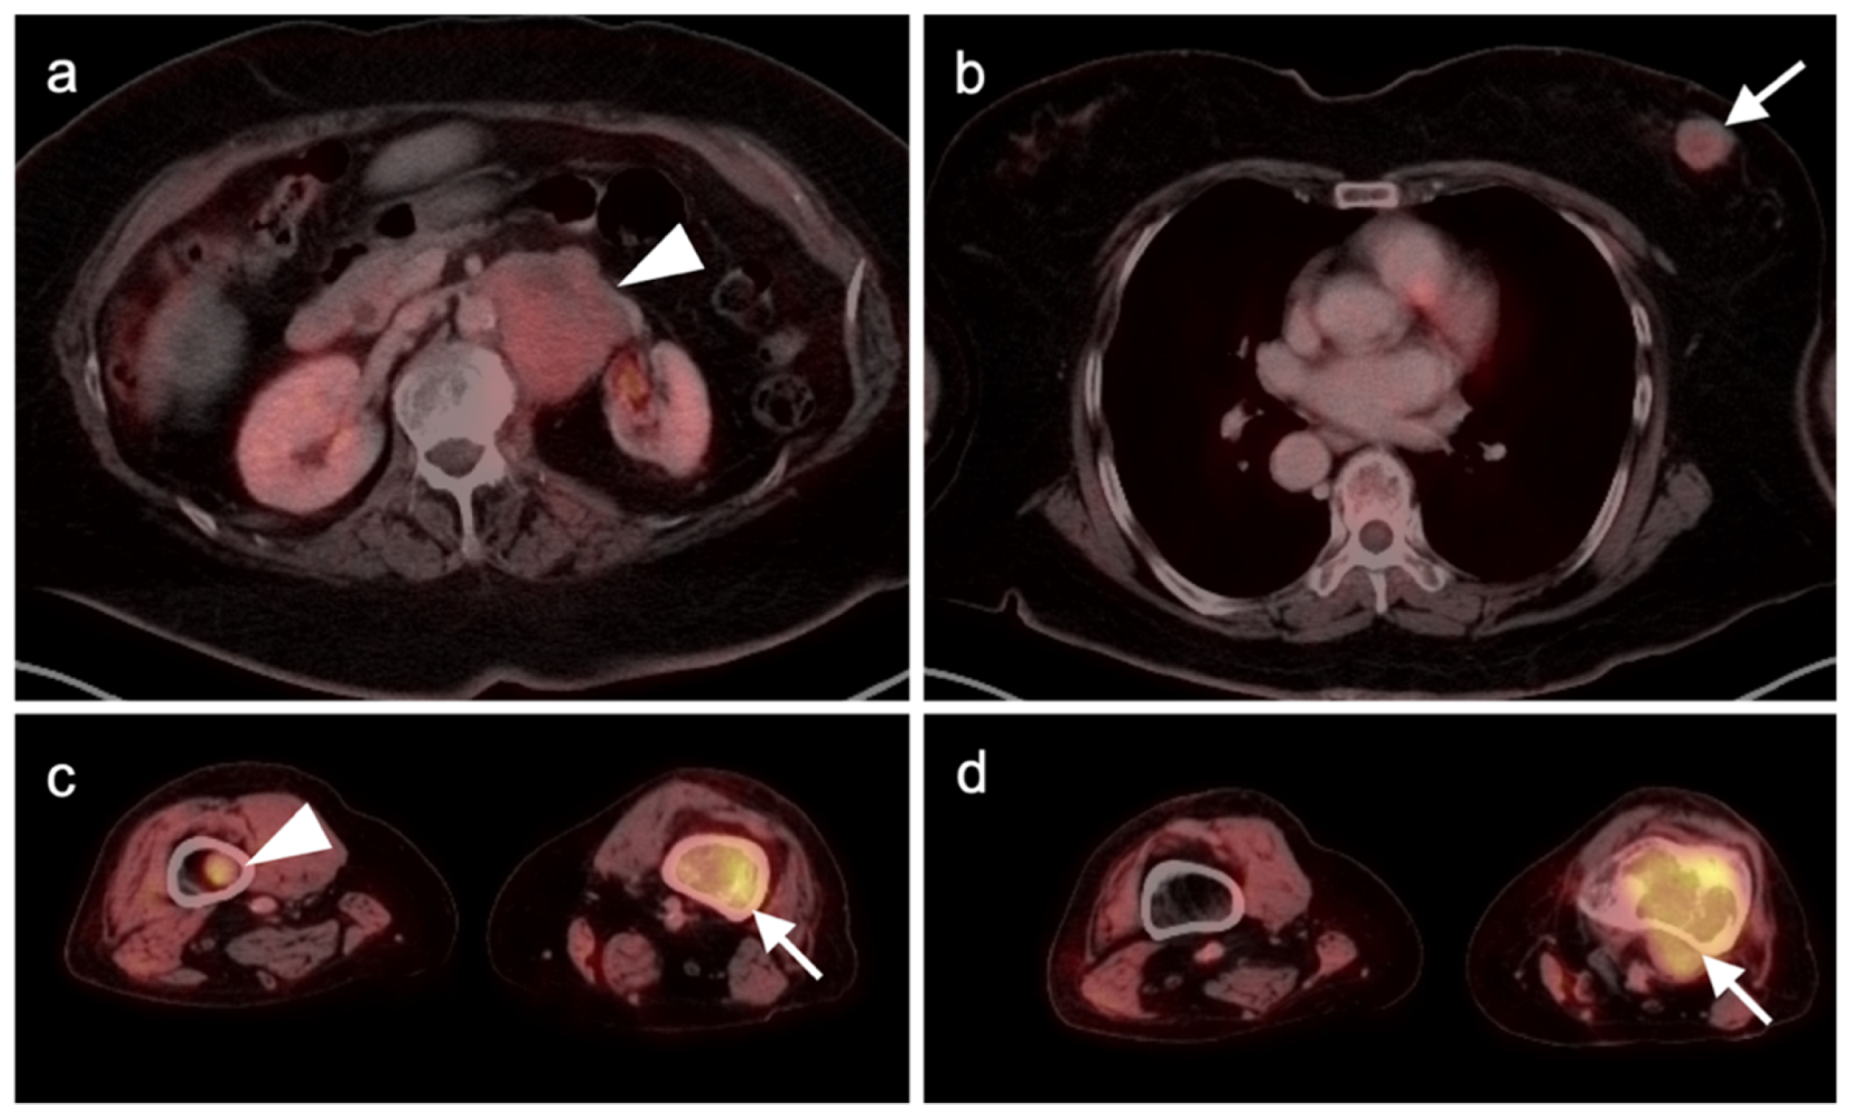

3.1.4. Kaposi Sarcoma